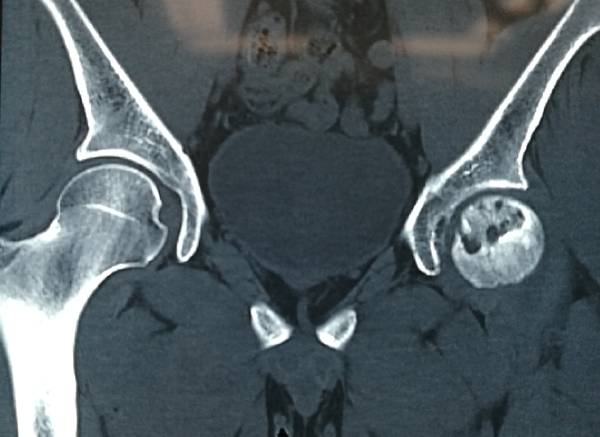

游离腓骨段切取术

移植治疗股骨头坏死

吻合旋股外侧动脉降支

IMG_20190115_125053.jpg

IMG_20190115_124548.jpg

IMG_20190115_121601.jpg